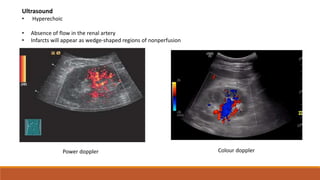

Power doppler Colour doppler

Ultrasound

• Hyperechoic

• Absence of flow in the renal artery

• Infarcts will appear as wedge-shaped regions of nonperfusion